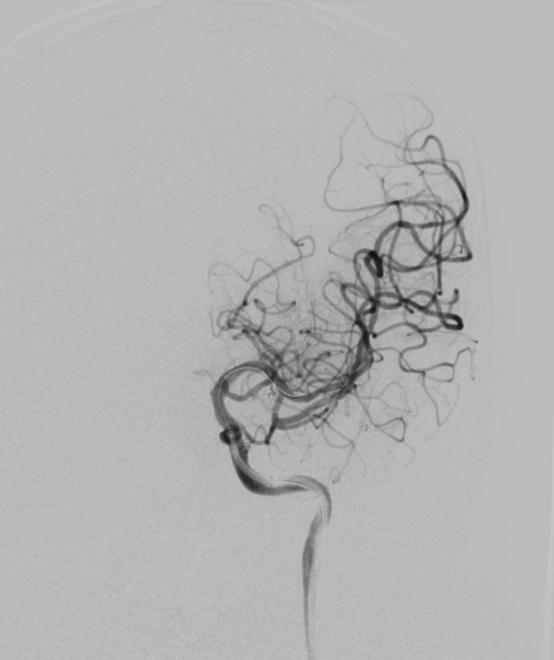

在转运的过程中,患者症状持续加重,完全失语、右侧肢体全瘫同时意识逐渐模糊。糟糕,一定是左侧颈内动脉闭塞后血流缓慢继发颅内血栓形成。时间就是大脑,为挽救李大哥的生命,民航总医院卒中团队高效运作起来,神经内科、血管介入科、麻醉科迅速完成了患者的转运、麻醉及造影。如术前所料,患者左侧颈内动脉C6段闭塞(图4、5),左侧大脑中动脉M2段血栓形成(图6)。一个一个环环相扣的动作,一个一个精细无间的配合,血管介入科团熟练的完成了取栓支架就位(图7)、取出大脑中动脉血栓、植入颈内动脉支架(图8)等一系列操作,成功的开通了血管,恢复了颅内的血流(图9、10)。

图9

图10